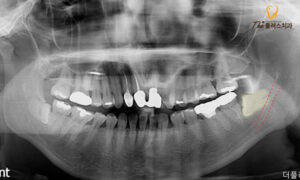

따라서 먼저 문제의 사랑니 발치 전

3D CT 촬영을 함께 진행하였고,

아래턱에 매복되어 있는 사랑니가

아래턱에 전반적으로 퍼져있는

하치조 신경과도 중첩되어 있어

확인 후 세심한 발치를 진행하였습니다.

또한 인접한 치아의 경우 사랑니 발치 후

상태를 확인해 보니 충치가 이미

신경까지 퍼져있어 추후 예후가 좋지 않아

다른 부위로 좋지 않은 영향을 줄 수 있어

발치를 진행하였습니다.